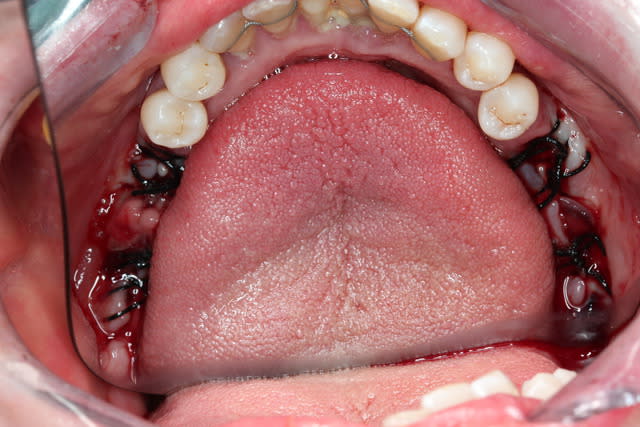

On a fait les PRfs et extractions des molaires maxillaires voici un mois

Et on vient d extraire le molaires inf avec PRFs ce jour

PS2 Message pour Olivier : quel traitement paro fais tu à cette patiente qd tu vois les pièces extractionnelles ?????